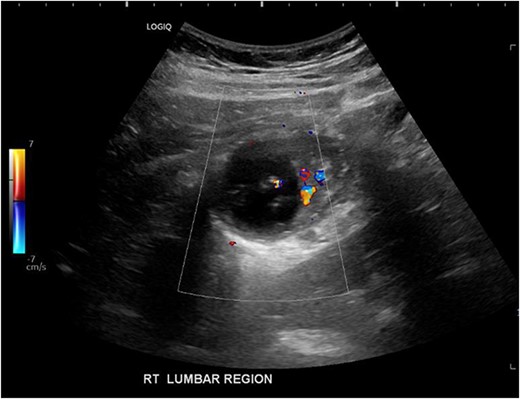

His white cell count was 12.7 × 109/L (reference range 3.7–9.5 × 109/L) and c-reactive protein was 39 mg/L (reference range ≤ 4 mg/L). Hydatid and entamoeba serologies were negative. Carcinoembryonic antigen was elevated to 11.4 ug/L (reference range ≤ 3 ug/L). Abdominal ultrasound showed an uncharacterizable RLQ cystic structure with calcification (Fig. 1). Subsequent computed tomography (CT) scan demonstrated a 56 mm × 43 mm × 58 mm ovoid ascending colon mass with central low density and rim enhancement (Fig. 2). Ileocolic lymphadenopathy up to 7.5 mm in diameter was noted with no evidence of distant metastatic disease.

Axial CT abdomen demonstrating a cystic submucosal lesion at the right colon (green arrow). There is involvement of the colonic lumen but no obstruction with oral contrasting passing through the lumen (blue arrow).

Diagnosis of colonic duplication cyst is reliant on radiology, intra-operative findings and histopathology. The typical finding on ultrasonography (US) is a cystic lesion with hypoechoic outer rim representing the smooth muscle layer [3, 7]. Endoscopic US may additionally demonstrate submucosa and mucosa as inner hyperechoic layers [3, 7]. CT typically demonstrates a fluid filled cystic lesion or a thin walled tubular structure. As in this case, a CT scan with oral contrast may be utilized to evaluate for bowel obstruction.